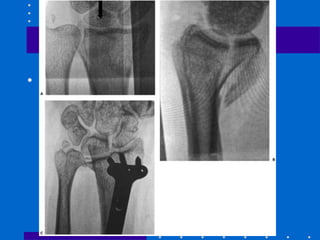

Fixação externa

• Em relação a gesso e pinagem neutralizaria

forças axiais dos flexores e extensores

• Fixador externo sozinho pode não ser

suficiente para prevenir algum grau de

colapso e perda da inclinação palmar

• Está se introduzindo fixadores que incluem

fragmento distal do rádio, sem fazer ponte

transarticularwww.traumatologiaeortopedia.com.br

Fixação externa + Enxerto

• Visam à remoção precoce do fixador

externo para reabilitação( cerca de 3

semanas) sem colapso ósseo

• Existem alguns estudos demonstrando bons

resultados utilizando osso esponjoso

autólogo, allograft ou cimento ósseo

Fixação externa + Pinagem

• Aumenta estabilidade e previne perda de

redução com relação ao FE isolado

• Maior complicação é lesão do nervo radial

superficial

• Fazer incisão de 5 mm e utilizar

hemostática para liberar trajeto